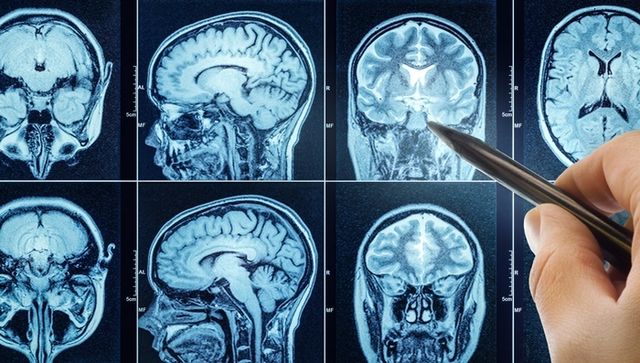

실제로 뇌종양은 증상이 없거나 매우 모호하게 나타나기 때문에 조기에 발견하기 어렵다. 뇌종양은 뇌 속에 생긴 비정상적인 세포 덩어리로, 양성과 악성으로 나뉜다.

양성 종양은 비교적 성장 속도가 느리고 다른 조직으로 퍼지지 않지만, 위치에 따라 신경을 압박해 다양한 증상을 유발할 수 있다. 반면 악성 종양은 빠르게 자라고 전이 가능성이 있으며, 생명에도 영향을 줄 수 있다.

뇌종양의 증상으로는 두통, 구토, 시야 장애, 기억력 저하, 성격 변화, 발작 등이 있으며, 초기에는 일반적인 피로나 스트레스로 오인될 수 있어 주기적인 검진이 중요하다.

뇌종양은 누구에게나 발생할 수 있는 질환이지만, 증상이 뚜렷하지 않고 초기 발견이 어려워 종종 치료 시기를 놓치게 된다. 김지석처럼 건강검진을 통해 조기에 발견하는 경우, 예후가 좋고 치료 부담도 낮다. 전문가들은 특히 40대 이후부터는 2~3년에 한 번씩 뇌 MRI를 포함한 종합 건강검진을 받을 것을 권장한다.

기사의 이해를 돕기 위한 사진 / Triff-shutterstock.com